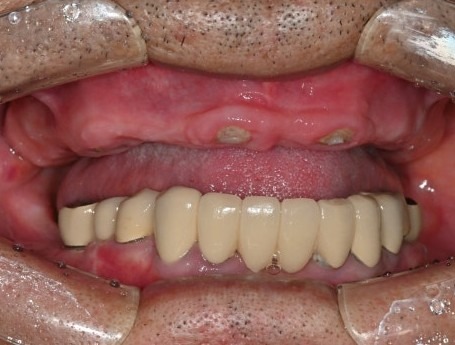

디지털 임시치아는

컴퓨터(CAD) 상에서 디자인하고

3D 프린터, 밀링 머신(CAM)으로 가공하기 때문에

손으로 빚어서 만드는 임시치아보다

훨씬 단단하고 심미적이며,

임시치아라고 해도 3개월,

길게는 1년 이상까지도 사용하면서

임플란트 치아에 적응하는 시간도 가질 수 있습니다.

"하루만에 치아가 다 생겼어요"

서울하늘에치과의 디지털 임시치아

좋은 계획과 기술로 만들어진 임시치아는

불과 몇 시간만에 환자분의 생활을

극적으로 달라지게 할 뿐만 아니라

환자와 의료진의 신뢰 관계를 증진시켜서

향후 치료 과정을 수월하게,

결과를 훌륭하게 만들 수 있습니다.